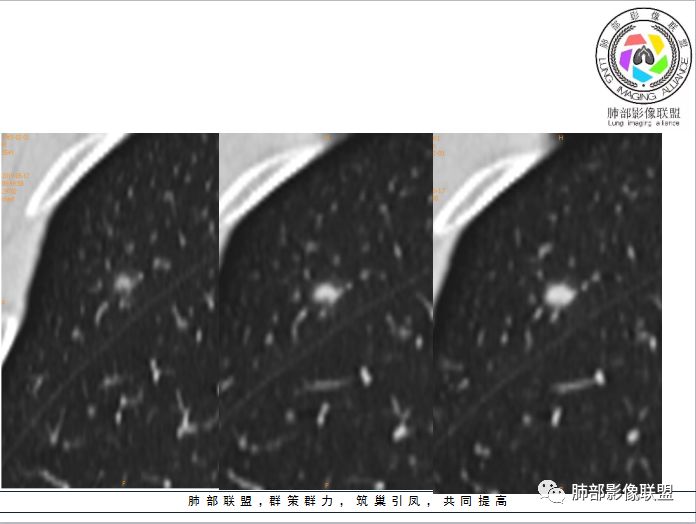

患者中年男性,体检发现。查肿瘤标志物、结核菌素实验、肝肾功能无明显异常。胸部CT:左肺上叶胸膜下类圆形实性结节,可见分叶、平直及血管贴边征象,周围可见磨玻璃影。综合考虑良性病变,隐球菌可能大,鉴别腺癌。

中年男性,平素体健,无呼吸异常主诉及体征,查血无明显异常。体检发现左肺上叶实性类圆形结节影,部分层面周围有磨玻璃晕症,可见血管进入,考虑良性,考虑炎性肉芽肿,考虑隐球菌感染可能,需与腺Ca、PSP鉴别

左上肺结节,边缘有晕,部分边缘清,部分模糊,无收缩力,贴血管边缘平直,考虑隐球菌可能 ,鉴别粘液腺癌。

左肺上叶结节,边缘光滑清晰,部分边缘平直,周围有晕,血管贴边,考虑炎性肉芽肿,隐球菌。鉴别浸润腺癌。

左肺上叶结节,轻度分叶,滋养血管征,晕中软毛刺,边缘偏模糊,考虑隐球菌,鉴别诊断黏液腺癌,晕偏一侧边缘偏清楚。

中年男性,左肺上叶类圆形实性结节,浅分叶、部分边缘平直,血管增粗贴边通过,周围晕征。实验室检查不支持结核,考虑炎性肉芽肿,隐球菌,鉴别腺癌。

孤立结节型隐球菌影像表现:

划重点:1、胸膜下、两下肺多见。

2、“3个1/3”:1/3与胸膜相连,1/3内部可见空泡征,1/3有晕征

3、“2个2/3”:2/3与胸膜有间隙,2/3近段与血管相连。